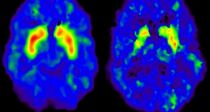

• ¾Æ »îÀÇ ¹«°Ô¡¦¿©¼º µîÅëÁõ ³²¼ºº¸´Ù ¾ÐµµÀû ¾Æ »îÀÇ ¹«°Ô¡¦¿©¼º µîÅëÁõ ³²¼ºº¸´Ù ¾ÐµµÀû Áö³­ÇØ µîÅëÁõÀ¸·Î Áø·á¸¦ ¹ÞÀº ¿©¼ºÀÇ ºñÀ²ÀÌ ³²¼ºº¸´Ù ´ëü·Î ³ô¾Ò´Ù. ƯÈ÷ 70´ë µîÅëÁõ ȯÀÚÀÇ °æ¿ì ¿©¼ºÀÌ ³²¼ºº¸´Ù µÎ ¹è ¸¹Àº °ÍÀ¸·Î ³ªÅ¸³µ´Ù. ±¹¹Î°Ç°­º¸Çè°ø´ÜÀÌ Á¶»çÇÑ ¡®2013³â ±âÁØ ¼º¡¤¿¬·É´ëº° µîÅëÁõ Áø·áÀÌ¿ë ÇöȲ¡¯¿¡ ...